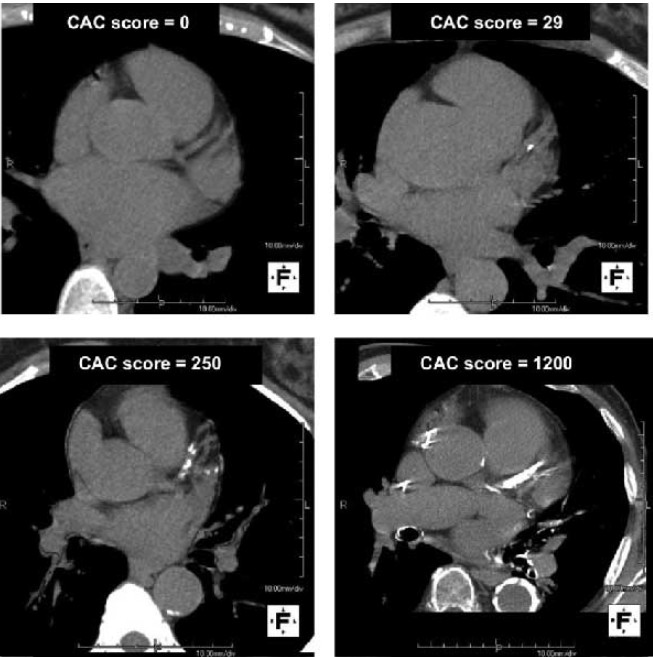

Examples of CAC Scores

These CT images demonstrate different Coronary Artery Calcium (CAC) scores. A score of

indicates no detectable calcium and a very low short-term risk.

As the score increases (e.g., 29, 250, 1200), more calcium is present in the coronary arteries, reflecting a greater plaque burden and increased cardiovascular risk. CAC scoring allows physicians to assess risk early and guide personalized prevention.